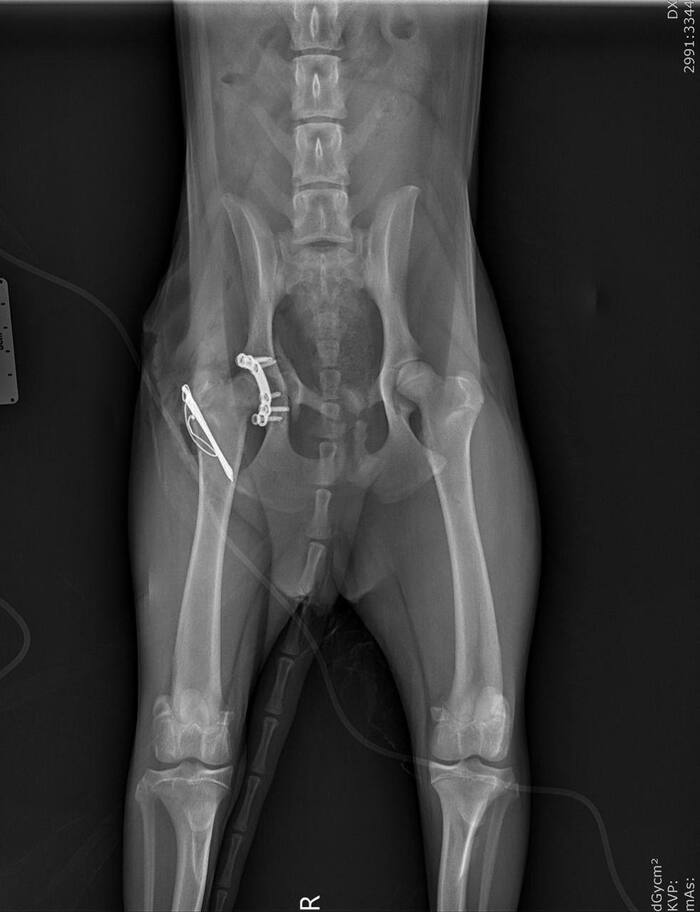

О нашей подопечной Боне мы уже писали. Это она — переломанная в автотравме у Боровского монастыря собака. Лечение продолжается, и суммы на него космические.

Бона попала под трактор несколько дней тому назад. Результат — скальпированная рана хвоста, множественные переломы опорно-двигательного аппарата. Все проблемы решаются постепенно: несколько дней назад была первая операция, на которой собрали переднюю лапу. Вчера ночью была проведена вторая операция, в ходе которой по кусочкам собирали таз и удалили часть хвоста.

Выше - вторая, вчерашняя операция. Ниже - первая, которая была пару дней назад (на нее ругается баянометр - снимок уже был в посте о Боне раньше, но не приложить его и сюда было бы неправильно).

Бона молодец. Пока на обезболивающих, и это неизбежно. Даже после всего произошедшего доверчиво тянется к людям, радуется поглаживаниям, наивно хлопает красивыми глазками. Уверены: пройдет положенное на восстановление время и Бона поправится. Чтобы искать самых Своих людей.